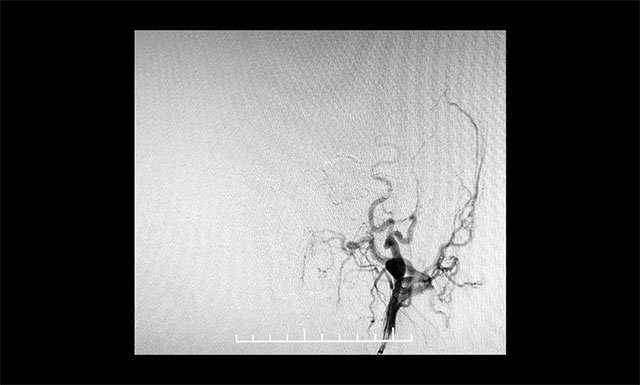

DSA 检查显示,左侧天幕区硬脑膜动静脉瘘,瘘口血流大,供血来源广泛,引流静脉有瘤样扩张。

▲ DSA检查显示,左侧天幕区硬脑膜动静脉瘘